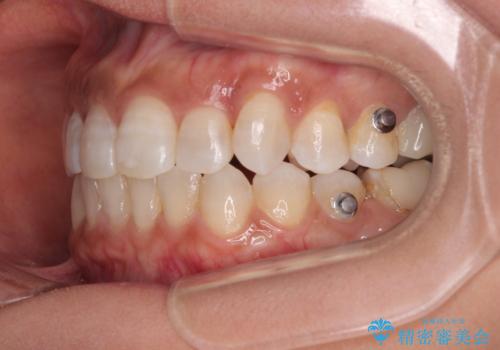

クロスバイトを治したい インビザラインによる矯正治療

- 前歯のクロスバイトを気にして来院された患者様です。

上下ともに、前歯部を中心にやや叢生が認められる程度であったため、ワイヤーでもインビザラインでも、どちらでも対応可能な状態でした。

咬合力が非常に強く、治療が進むにつれて上下奥歯が離開してくることが予想されるため、治療途中から上下の顎間ゴムを使用することを理解いただき、インビザラインによる矯正治療を行うこととしました。

咬合力による臼歯離開は顎間ゴムで改善されましたが、それとは別に下顎小臼歯がマウスピースに追従せず、補正のためのゴムかけが必要となりました。

大変なゴムかけ作業を頑張っていただき、無事に治療を終えることができました。